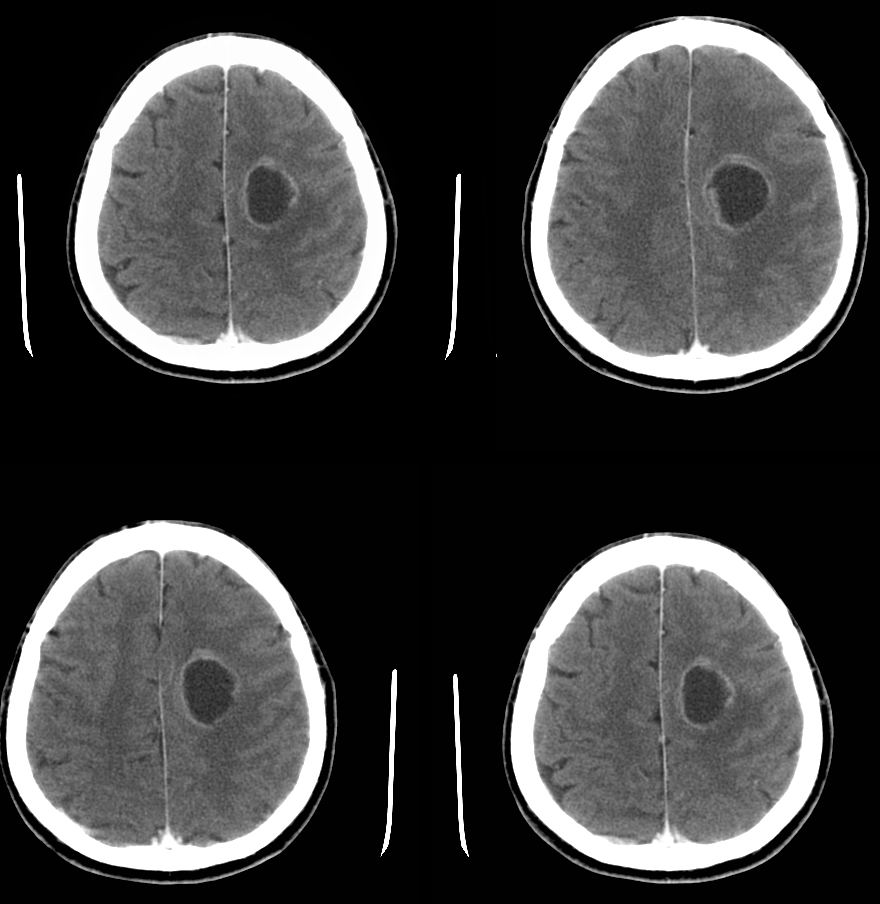

以下是引用zyx168在2007-9-1 7:00:00的发言:[br]首先考虑脑脓肿。此例从影像与临床很难鉴别:胶质瘤,囊虫病,转移瘤。

以下是引用zjzjr在2007-8-31 22:26:00的发言:[br]病灶呈薄壁环形强化,未见壁结节,支持脑脓肿可能性大.

以下是引用liuhongjun01在2007-9-1 11:12:00的发言:[br]病灶呈囊状有轻度占位,增强后呈环形薄壁强化,没有明显壁结节影,病灶位于半卵圆中心,[br]与硬脑膜无关系,考虑慢性脑脓肿,请结合临床,须与脑囊虫病、肿瘤等鉴别,单凭影像难肯定诊断。